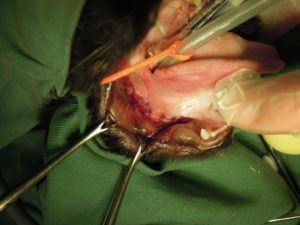

5.周囲をきれいにして縫合します。

6.右側下顎も臼歯を抜歯・縫合します。